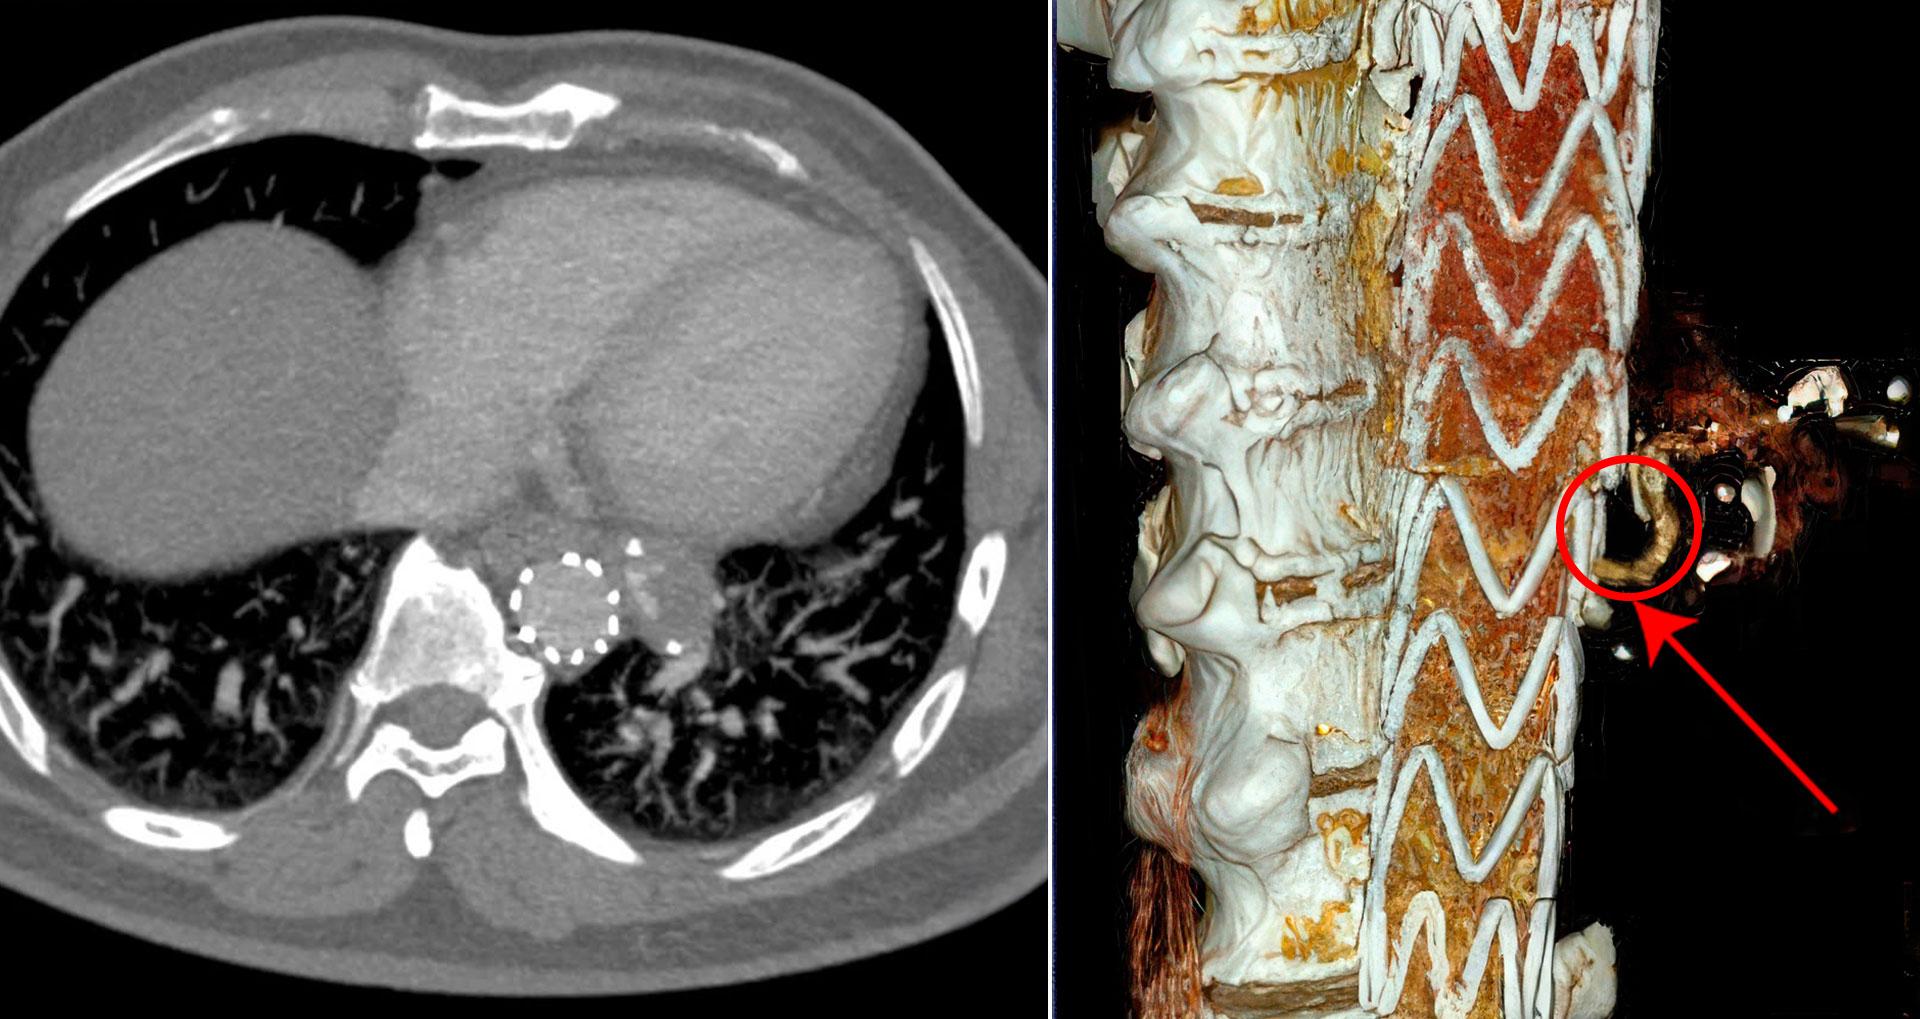

TS.BS Vũ Hữu Khiêm, Trưởng khoa Ung bướu, BVĐK Tâm Anh Hà Nội, cho biết siêu máy có số lượng lát cắt không giới hạn, mỗi lát cắt có độ dày chỉ 0,4mm, giúp phát hiện các tổn thương rất sớm ở phổi, gan, thận, xương... Bác sĩ có thể tùy chỉnh số lượng lát cắt tùy nhu cầu chụp theo vùng nhỏ, vùng lớn hay toàn thân, từ đó đánh giá được rất sớm các nốt ở phổi, gan, các khối u tại chỗ hoặc có di căn.

TTND.PGS.TS.BS.CKII Nguyễn Hữu Ước, Trưởng khoa Phẫu thuật Tim, Mạch máu và Lồng ngực BVĐK Tâm Anh Hà Nội, cho biết với những khối u rất nhỏ, giai đoạn sớm, mới ở dạng nốt hoặc kính mờ, thường mờ nhòe, khó đọc trên máy CT thông thường.

Nhưng với siêu máy này, độ phân giải cao cho hình ảnh sắc nét, giúp bác sĩ nhận định đúng có khối u hay không, khả năng lành hay ác tính, từ đó đưa ra quyết định điều trị phù hợp. Đây là công dụng quan trọng, có ý nghĩa lớn trong chẩn đoán và điều trị các bệnh lý ung thư. Như với ung thư phổi, nếu phát hiện giai đoạn sớm và phẫu thuật kịp thời, người bệnh có cơ hội sống trên 10 năm rất cao.